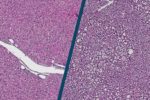

Bakteriophagen zerstören gezielt multiresistente Keime. Gerade bei Antibiotikaresistenz haben sie deshalb großes Potenzial. Ihre Anwendungsperspektiven wurden jetzt umfassend bewertet.